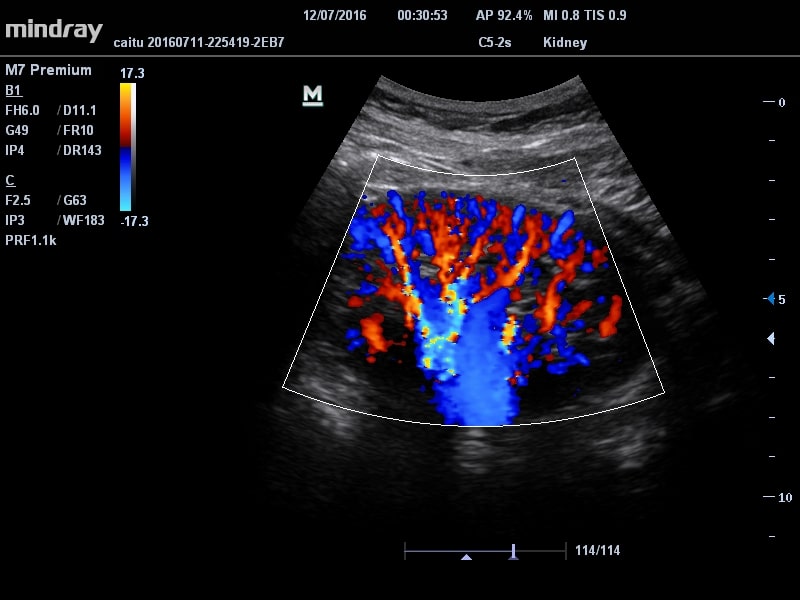

Ультразвуковой сканер Mindray M7 Premium

- CFM – цветное допплеровское картирование, изучение характера кровотока;

- HR Flow (Режим отображения кровотока с высоким пространственным разрешением)